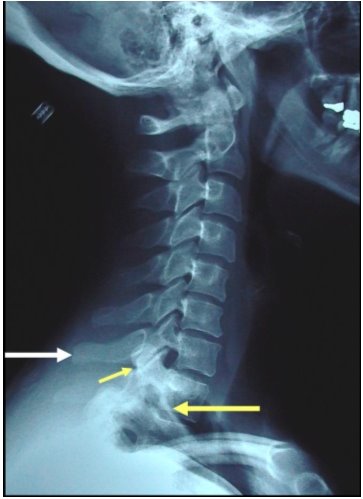

Узлы шморля th12

Узлы шморля th12 113 фото